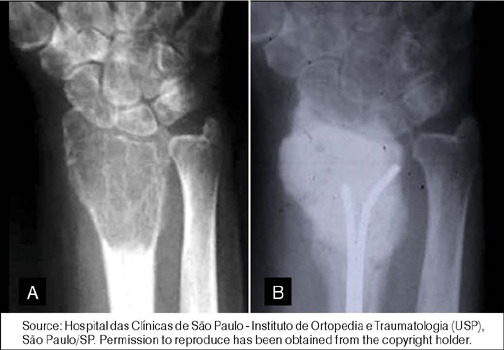

Abstract Image